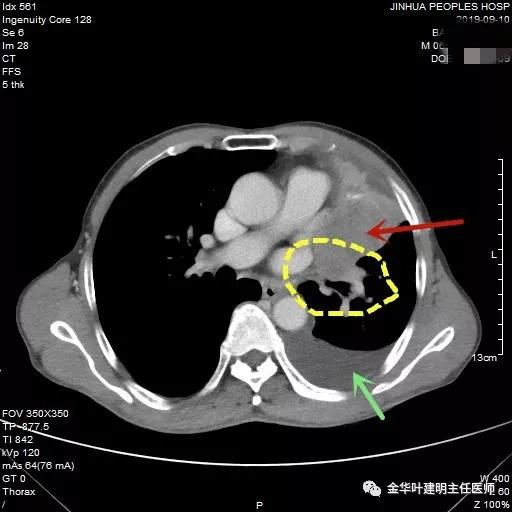

黄色区域示左下叶支气管受压,与肿瘤间没有间隙

肿瘤巨大,并与心脏关系密切,提示可能需切开心包处理